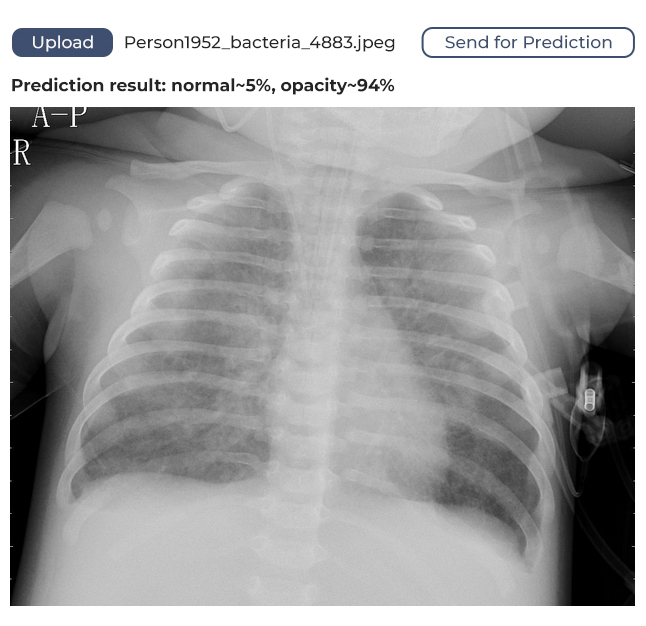

The model we’ve developed has a margin of confidence and uses binary identification. What does this mean? It means if the algorithm identifies 80% of lungs as unaffected, it will say the lungs are healthy. If the figure is below 80%, it will assume the lungs might be affected and require medical attention.

How It Works

The user opens the web application in their browser, uploads a lung image, sends it to the service, and receives feedback. The feedback will show whether the lungs are healthy or if a doctor should take a look at the image.